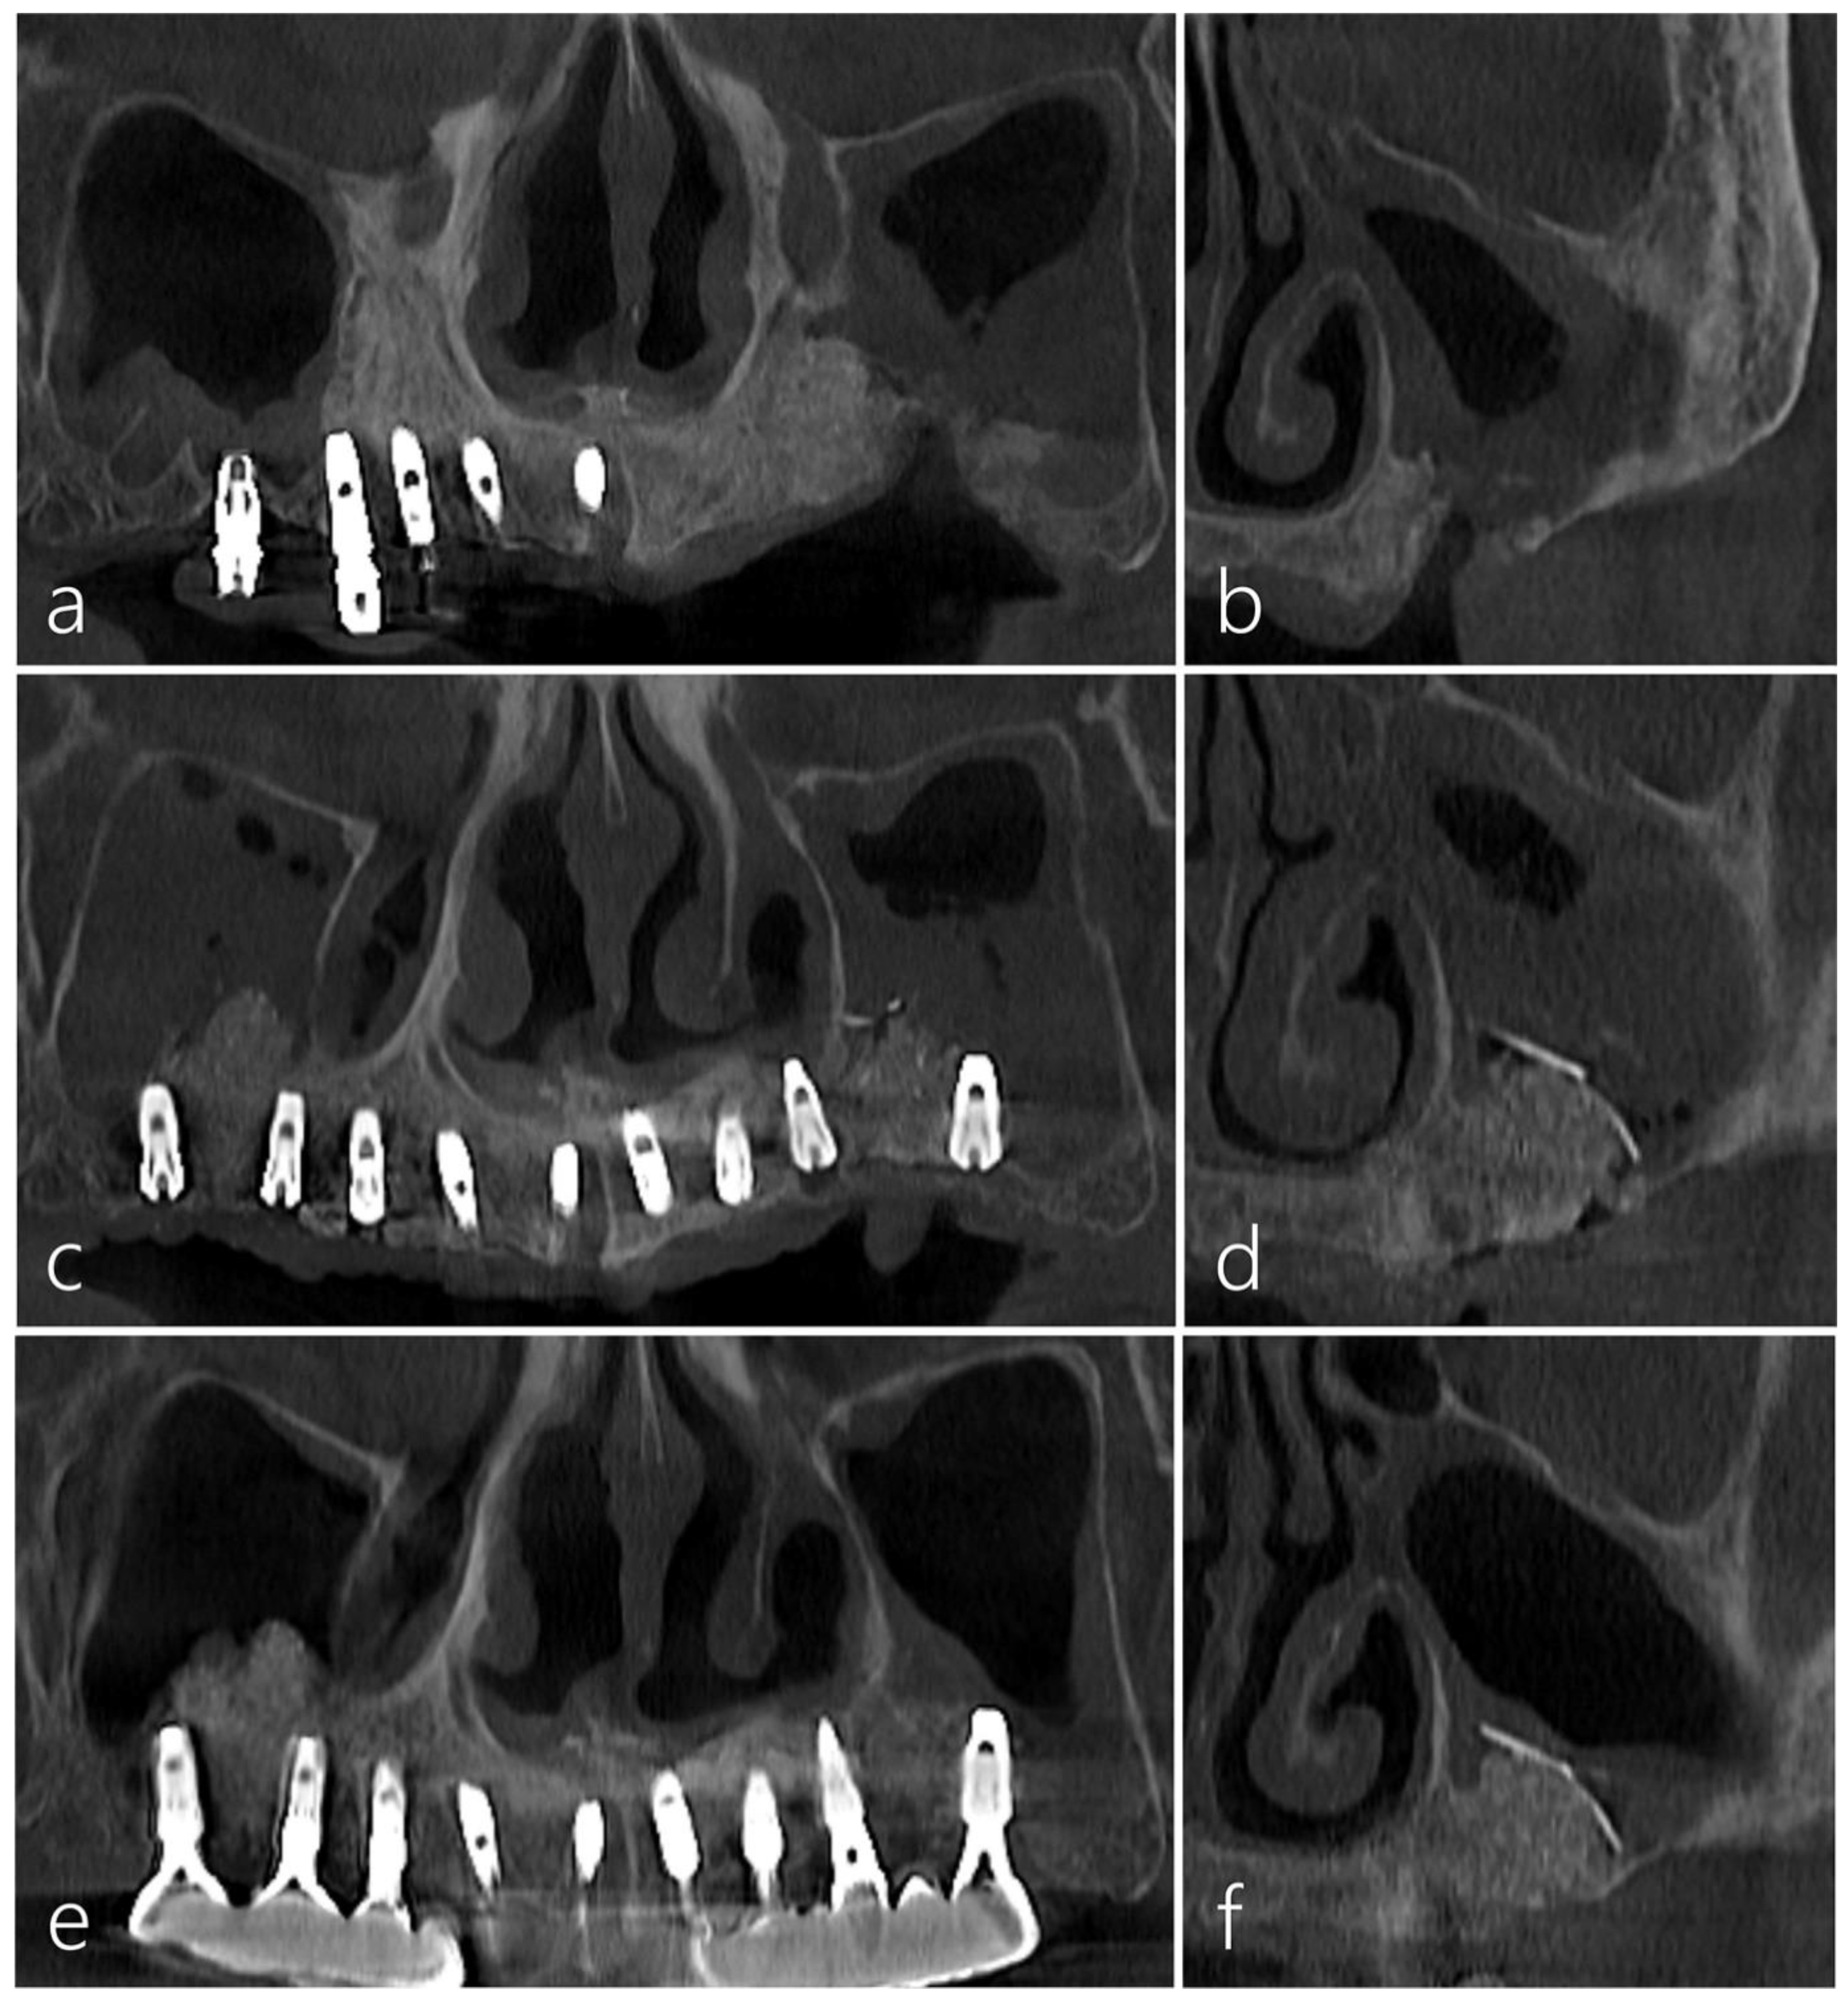

2.2. Case 2